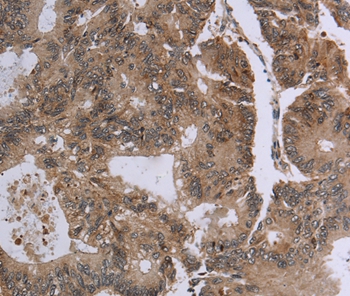

Immunohistochemical analysis of paraffin-embedded Human colon cancer tissue using #37575 at dilution 1/20.